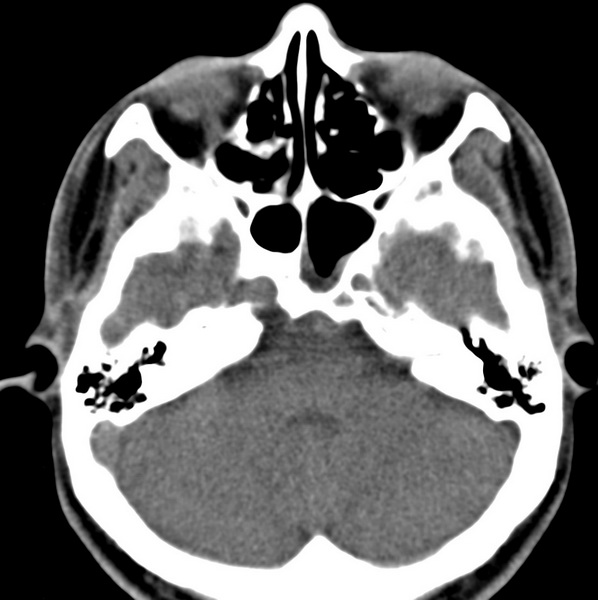

男、31、鼻咽部肿瘤放疗后请帮忙看看。

效果好,右侧破裂孔扩大,局部骨质缺损,为颅底骨质破坏。

1)鼻咽部肿瘤侵犯颅底放疗术后改变。2)左侧蝶窦炎。

咽后壁增厚,左侧咽鼓管隆突增大、咽鼓管咽口变浅,同侧咽旁间隙较窄。右侧颅底骨质破坏?为什么不在同一侧?

鼻咽部肿瘤侵犯颅底放疗术后改变.